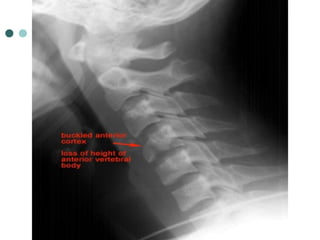

WEDGE FRACTURE

 Compression fracture resulting from flexion

 Mechanism: Hyperflexion and compression

 Signs:

 Buckled anterior cortex

 Loss of height of anterior vertebral body

 Anterosuperior fracture of vertebral body

 stable